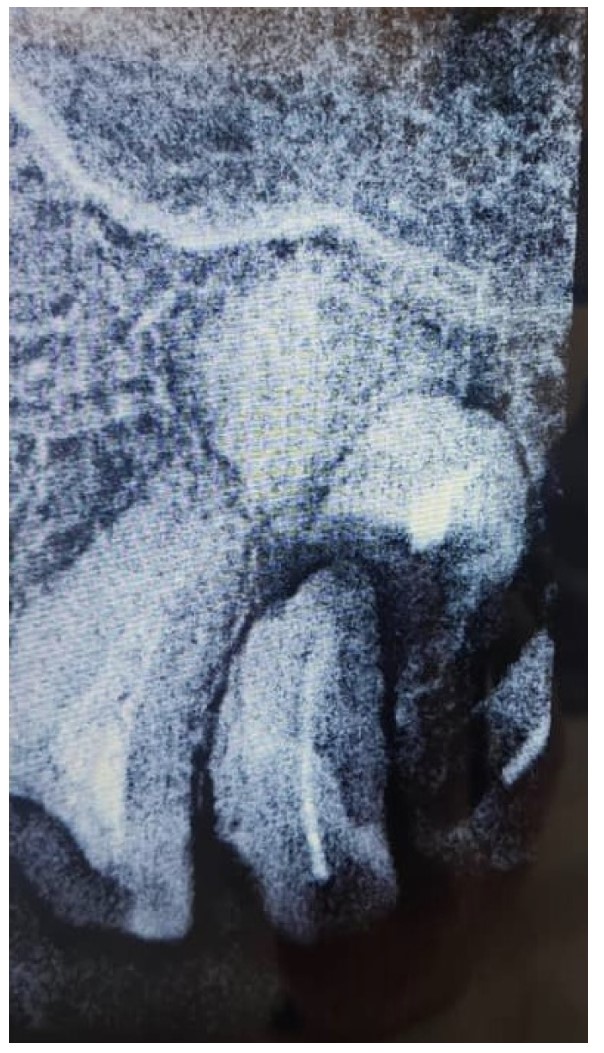

Periapical view of the maxillary molar region showing unrestorable roots, as well as a radiopaque lesion on the periapical plane that was not noticed during the preoperative radiograph.

Two MegaGen ST implants (MegaGen Implant Company, South Korea) were placed. At the four-month follow-up, the maxillary first molar implant was exposed, with a significant periodontal pocket detected around it despite stability. OPG revealed bone resorption around the implant (Fig. 7), and CBCT identified a 0.5 mm radiopaque mass resembling residual roots. The implant was removed, the mass was excised, and the area was cleaned. Histological analysis confirmed osteosclerosis (Fig. 8).

Preoperative scan showing the location of the lesion noted when reviewing scans after implant failure.

OPG 6 months after surgery showing significant bone resorption around the dental implant.

In contrast, the second case resulted in implant failure, with significant bone loss observed around the implant placed in proximity to an IO lesion. This divergent outcome underscores the unpredictable nature of IO in clinical practice and suggests that the relationship between sclerotic bone and implant success may be more complex than simple mechanical considerations. The failure in this case may be attributed to several factors, including possible compromised blood supply in the sclerotic region, altered bone remodeling capacity, or excessive occlusal forces concentrated in the area of abnormal bone density. The finding that the lesion was initially mistaken for a residual root fragment further emphasizes the diagnostic challenges posed by IO and the importance of thorough radiographic evaluation prior to implant placement [26-28].